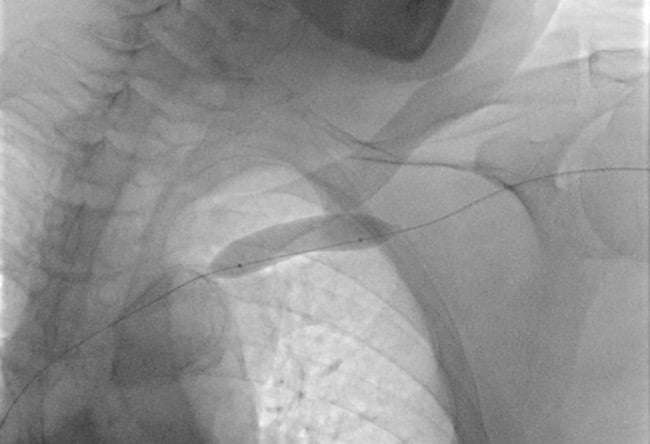

We decided to perform an access in the left basilic vein to achieve a more favourable angle (5).

Using a 0.018” Halberd guidewire and a support catheter, we successfully recanalised the intrastent occlusion.

A snare catheter was used to establish a through-and-through access between basilic and femoral access (6).

With the through-and-through guidewire, we advanced the 7F introducer sheath from the femoral venous access inside the occlusion (7).

A second through-and-through wire was then placed (8), reaching the cephalic vein lumen, the distal target of our intervention.